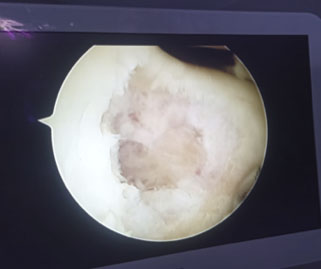

Infarto óseo surco troclear